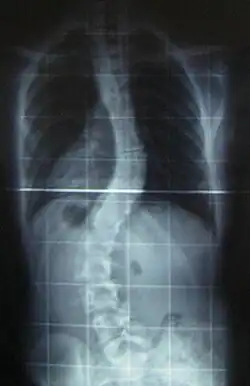

When scoliosis is suspected, weight-bearing, full-spine AP/coronal (front-back view) and lateral/sagittal (side view) X-rays are usually taken to assess the scoliosis curves and the kyphosis and lordosis, as these can also be affected in individuals with scoliosis. Full-length standing spine X-rays are the standard method for evaluating the severity and progression of the scoliosis, and whether it is congenital or idiopathic in nature. In growing individuals, serial radiographs are obtained at 3- to 12-month intervals to follow curve progression, and, in some instances, MRI investigation is warranted to look at the spinal cord.[35]

The standard method for assessing the curvature quantitatively is measuring the Cobb angle, which is the angle between two lines, drawn perpendicular to the upper endplate of the uppermost vertebra involved and the lower endplate of the lowest vertebra involved. For people with two curves, Cobb angles are followed for both curves. In some people, lateral-bending X-rays are obtained to assess the flexibility of the curves or the primary and compensatory curves.